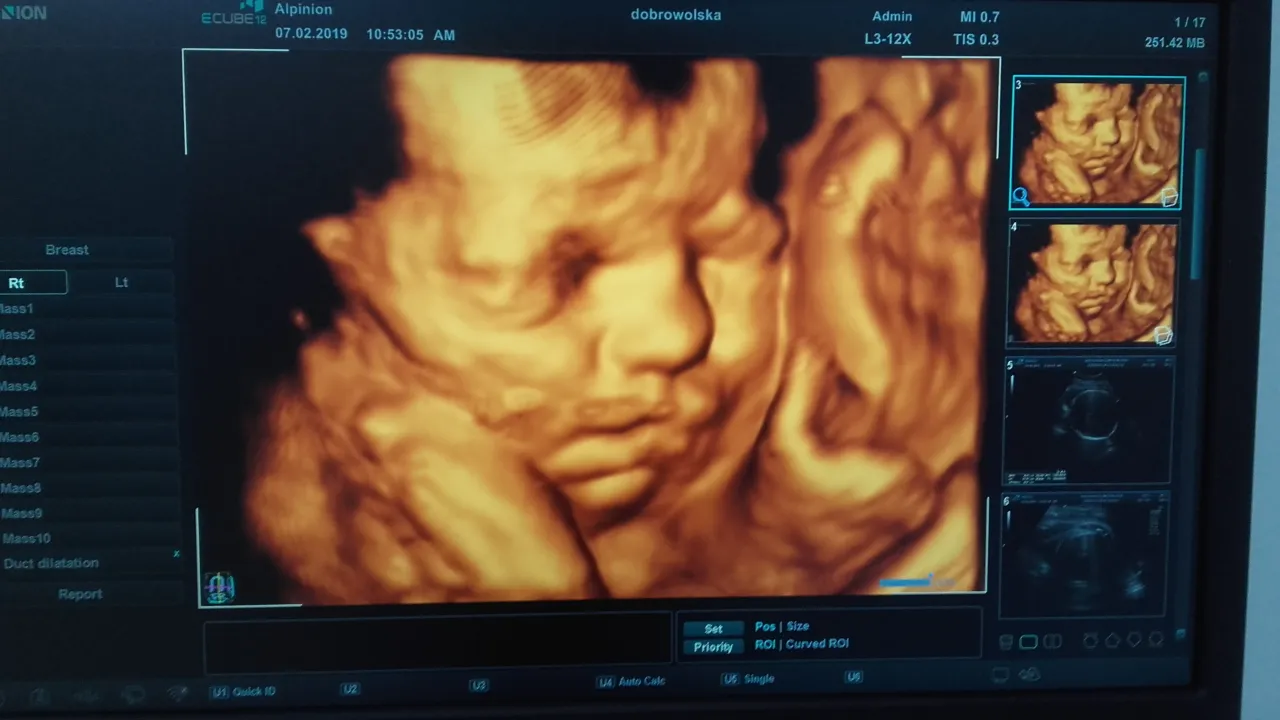

USG 3D/4D a płeć dziecka: Czy lepszy obraz oznacza większą pewność?

Badania USG 3D/4D, które dostarczają bardziej realistycznych, trójwymiarowych obrazów dziecka, są dla wielu rodziców niezwykłym przeżyciem. Czy jednak oznaczają większą pewność w określeniu płci? W praktyce, choć obraz jest bardziej widowiskowy, w kontekście samej płci nie zawsze dają one znacząco większą pewność niż dobrej jakości USG 2D. Jeśli dziecko jest źle ułożone, nawet najlepsze technologie 3D czy 4D nie pomogą zajrzeć tam, gdzie maluszek się "schował". Główną zaletą 3D/4D jest więc wizualizacja i możliwość zobaczenia rysów twarzy dziecka, a niekoniecznie precyzja w tym konkretnym aspekcie.